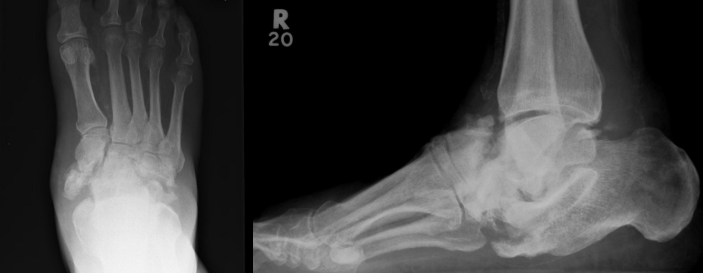

Foot & Ankle Fractures

- Overview: Traumatic injuries to the ankle, midfoot, or forefoot can lead to joint instability and arthritis if not properly treated.

- Treatment: We utilize modern fixation techniques (plates, screws, intramedullary nails, and external frames) to achieve precise alignment and promote bone healing.

- Goal: Restore anatomic alignment, maintain joint function, and allow early rehabilitation.